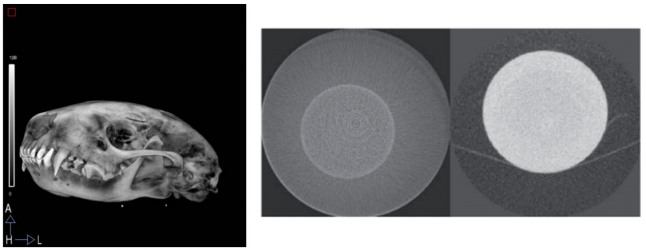

| ABSTRACT | Introduction: Simultaneous in-vivo imaging of several biological processes may improve oncological, neurological and cardiovascular studies by providing complementary information obtained under the same exact conditions and coregistered in space and time. Standard PET imaging does not allow multiplexed acquisitions, as all annihilation photons have the same energy. We developed a technique called multiplexed PET (mPET), which uses a tracer labelled with a pure positron emitter (such as 18 F, 13 N, 11 C), and a tracer labeled with a positrongamma emitter (such as 124 I, 76 Br, 82 Rb, 86 Y). Positrongamma emitters generate a significant number of triplecoincidences , which allows them to be differentiated from the standard PET radionuclides . In this work, we evaluated the performance of mPET using phantom and animal experiments. |